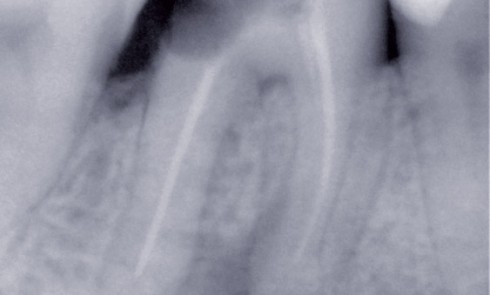

Article réservé à nos abonnés Le pilier prothétique : faut-il traiter ou implanter ?

Le pilier prothétique est indispensable à la prothèse fixée. Sa pérennité dans le temps est un critère majeur dans la...